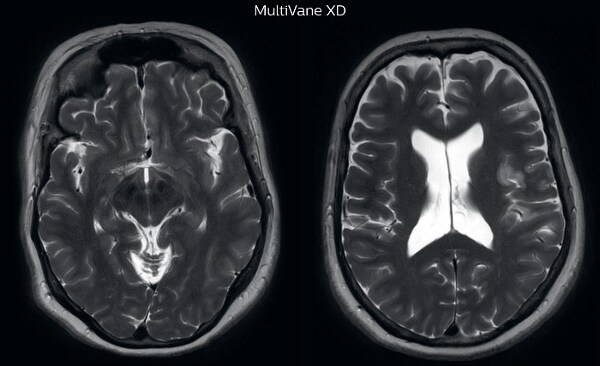

The images made with MultiVane XD show significant reduction in motion artifact compared to the T2-weighted images without MultiVane below them.   Scanned on Ingenia 3.0T